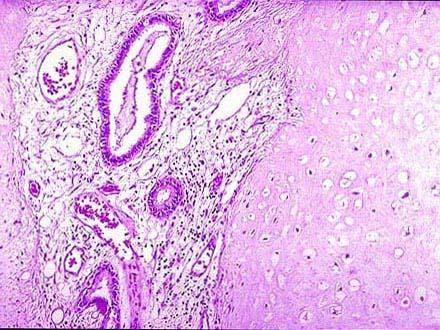

问题 患者女性,24岁,体检时发现肺部有一高密度影,手术切除,术中见肿块境界不清,无包膜,病检镜下如图所示:肿块由增生的软骨,血管,纤维组织,腺腔等组成。可能的诊断是 ( )

选项 A.肺腺癌 B.肺结核球 C.肺转移瘤 D.肺错构瘤 E.肺鳞状细胞癌

答案 D